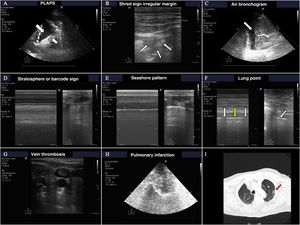

The most frequent findings in patients with acute respiratory failure.

A) Images of PLAPS, showing hypoechoic zones delimiting a poorly defined margin (small arrow) and pleural effusion (large arrow). B) Subpleural consolidation comprising a hypoechoic zone in contact with the pleural line surrounded by an irregular hyperechoic margin (shred sign). C) Air bronchogram showing hyperechoic lines (small arrow) in the context of lung hepatization, surrounded by adjacent pleural effusion (large arrow). D) Bar code pattern (stratosphere sign) in M mode, corresponding to pneumothorax. E) Seashore pattern in a lung with preserved pleural sliding. F) M mode positioned (left) in the zone corresponding to the lung point (arrow, image at right). Oscillation is observed of the seashore (white arrows) and barcode patterns (yellow arrows) in relation to the inspiratory and expiratory phases. G) Thrombus in the internal jugular vein, manifesting as a hyperechoic image occupying most of the vascular lumen. H) Pulmonary infarction: hypoechoic zone, containing a hyperechoic image (obtained with a low-frequency probe), corresponding to the bronchial tree. I) Pulmonary infarction zone (red arrow) in the lung computed tomography scan of the same patient.

The sensitivity of ultrasound in detecting pneumothorax is greater than that of conventional radiological and similar to that of CT.3,4

The ultrasound exploration of pneumothorax yields the following findings:

Absence of lung sliding.

Absence of B lines (as there is no lung parenchyma immediately below the pleural line).

Change in the normal pattern in M mode from the “seashore” pattern to the “barcode” or “stratosphere” sign. A series of parallel lines of variable thickness are observed (Fig. 2). This sign may also appear on exploring large bullae that can be confused with pneumothorax.

Presence of the so-called lung point, which is seen when pneumothorax is not massive. This sign is characterized by the appearance of lung in 2D imaging in inspiration, with disappearance in expiration - corresponding to the point where the visceral and parietal pleural layers separate from each other. It can also be found as changes in M mode, consisting of a transition from the “seashore” pattern to a “barcode” pattern in successive respiratory cycles (Fig. 2 and video 1 of the electronic supplementary material [ESM]). Its specificity in diagnosing pneumothorax is 100%.

PneumoniaThe ultrasound diagnosis of pneumonia is based on identification of the B', A/B and C patterns. The presence of PLAPS adds diagnostic precision. It is very important to find subpleural condensations in the anterior lung fields, characterized by hypoechoic zones in contact with the pleural line.5 These hypoechoic zones present irregular margins, referred to as the fractal or shred sign (Fig. 2).

The appearance of a mobile or dynamic air bronchogram points to the diagnosis of pneumonia. This consists of linear hypoechoic images, sometimes with a ramified appearance, that displace with breathing if the corresponding airway is patent. The image is produced by gas penetration into the bronchial tree containing secretions (Fig. 2 and video 2 ESM).

Pulmonary thromboembolismIn the context of a patient with respiratory failure, the bilateral A pattern of the BLUE protocol implies a possible diagnosis of pulmonary embolism This exploration is complemented by vascular evaluation in search of venous thrombosis (Fig. 2) and cardiac exploration in search of signs of dysfunction or dilatation of the right ventricle.

Another possible ultrasound finding related to pulmonary embolism is the image of lung infarction, characterized by a hypoechoic, triangular subpleural zone6 (Fig. 2).